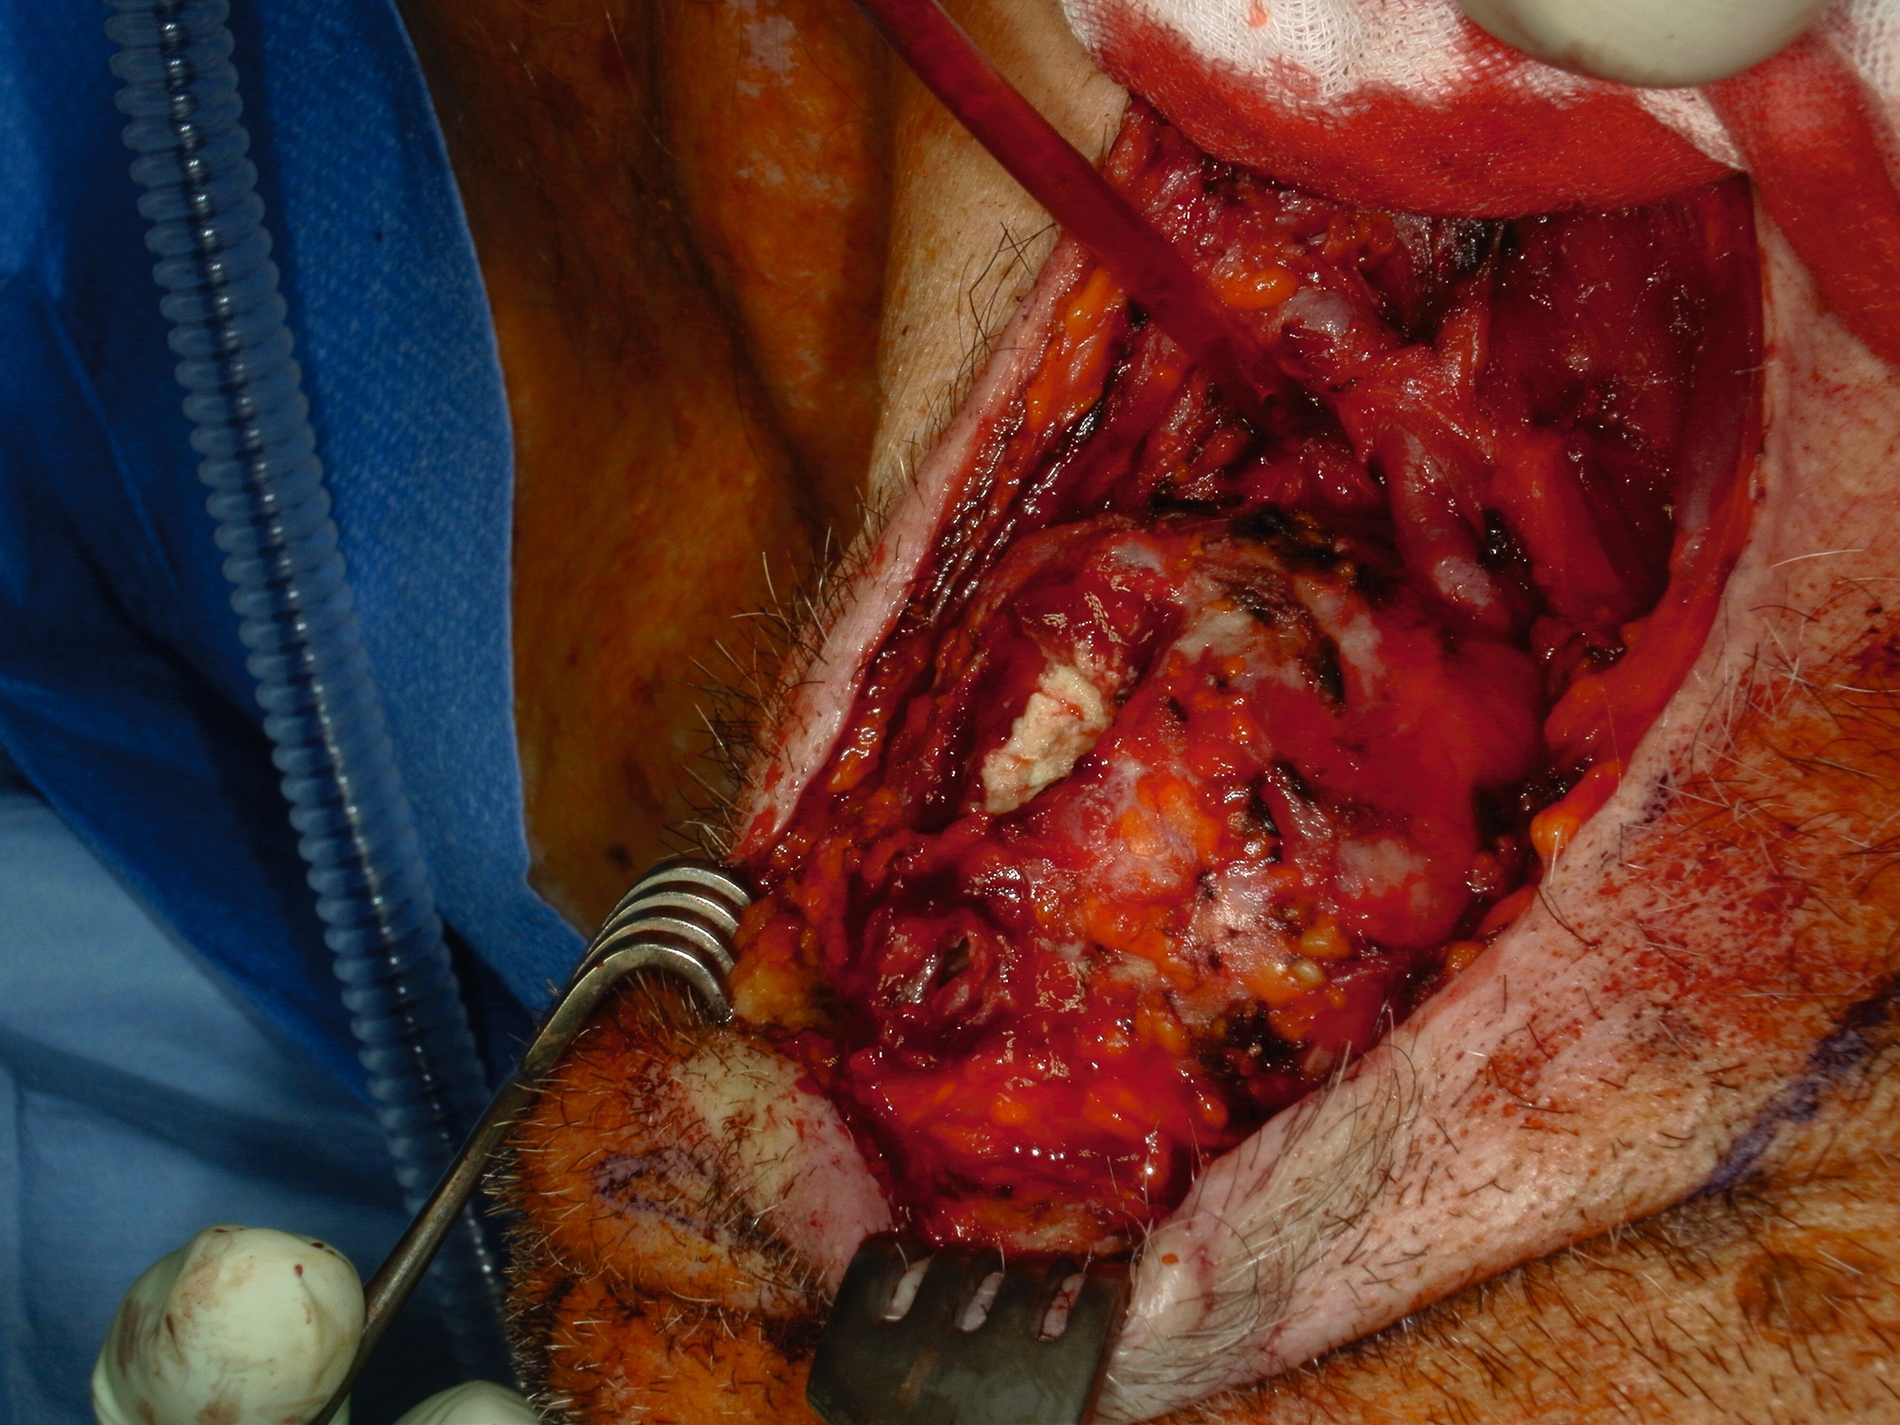

Eine kontrastmittelgestützte Computertomografie (CT) zeigte eine 6 cm x 5 cm x 4 cm große Raumforderung submandibulär rechts mit inhomogener Kontrastmittelaufnahme und teils zystischer Binnenstruktur (Abbildung 1). Der Befund wies morphologisch auf eine maligne Genese hin. Ein weiterführendes Staging mittels CT-Thorax und Abdomen zeigte keine Anzeichen für Fernmetastasen oder weitergehende Lymphknotenmanifestationen. Dem Patienten wurde die Indikation zur operativen Entfernung der Raumforderung im Sinne einer erweiterten Exzisionsbiopsie erläutert. Es wurde mit ihm besprochen, dass bei intraoperativem Nachweis eines malignen Befunds eine onkologische Resektion mit Sicherheitsabstand sowie eine elektive Neck Dissection der Level II–IV erfolgen würde. Ebenso wurden verschiedene Rekonstruktionsmöglichkeiten für den Fall eines größeren Defekts erörtert.